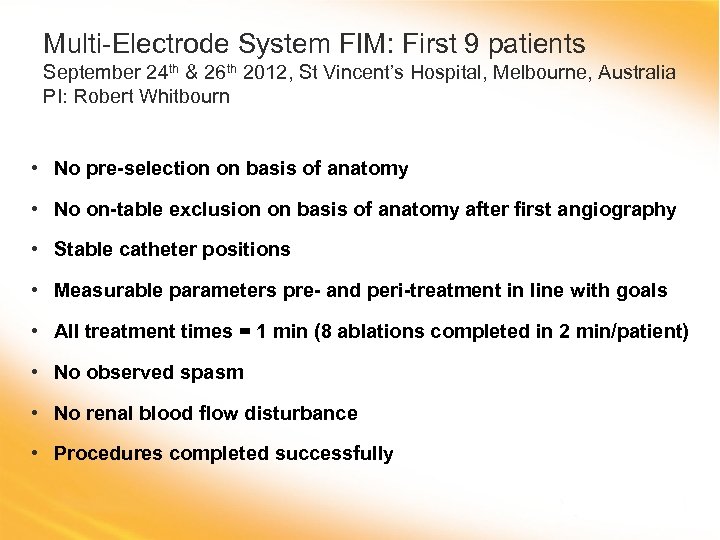

Multi-Electrode System FIM: First 9 patients September 24 th & 26 th 2012, St Vincent’s Hospital, Melbourne, Australia PI: Robert Whitbourn • No pre-selection on basis of anatomy • No on-table exclusion on basis of anatomy after first angiography • Stable catheter positions • Measurable parameters pre- and peri-treatment in line with goals • All treatment times = 1 min (8 ablations completed in 2 min/patient) • No observed spasm • No renal blood flow disturbance • Procedures completed successfully

Multi-Electrode System FIM: First 9 patients September 24 th & 26 th 2012, St Vincent’s Hospital, Melbourne, Australia PI: Robert Whitbourn • No pre-selection on basis of anatomy • No on-table exclusion on basis of anatomy after first angiography • Stable catheter positions • Measurable parameters pre- and peri-treatment in line with goals • All treatment times = 1 min (8 ablations completed in 2 min/patient) • No observed spasm • No renal blood flow disturbance • Procedures completed successfully